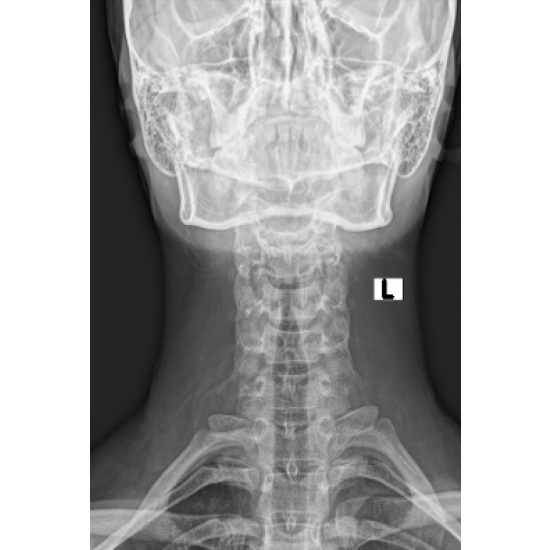

XR 4+ view cervical spine: Normal vertebral body and disc height. No acute osseous abnormality. Case Photo #1 , Case Photo #2 , Case Photo #3 , Case Photo #4